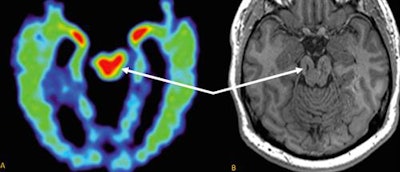

In comparing the two MRI scans, the researchers visually noticed areas of T1 hypointense and T2 hyperintense foci of encephalomalacia in the midbrain of the brainstem, which is consistent with atrophy. In addition, total gray-matter volume decreased by 14% over that time. The largest volume shrinkage was in the ventral diencephalon (-10.3%), followed by the frontal lobes (-3.6%) and the brainstem (-2.7%).

"The reason [volume loss] happens in the midbrain is because the force of football impacts are triangulated into that region," Raji explained. "The frontal lobes are affected because they are literally right behind the skull when the person is hitting their head. The ventral diencephalon sits on top of the brainstem, so it also makes sense that that region of the brain is affected as well."